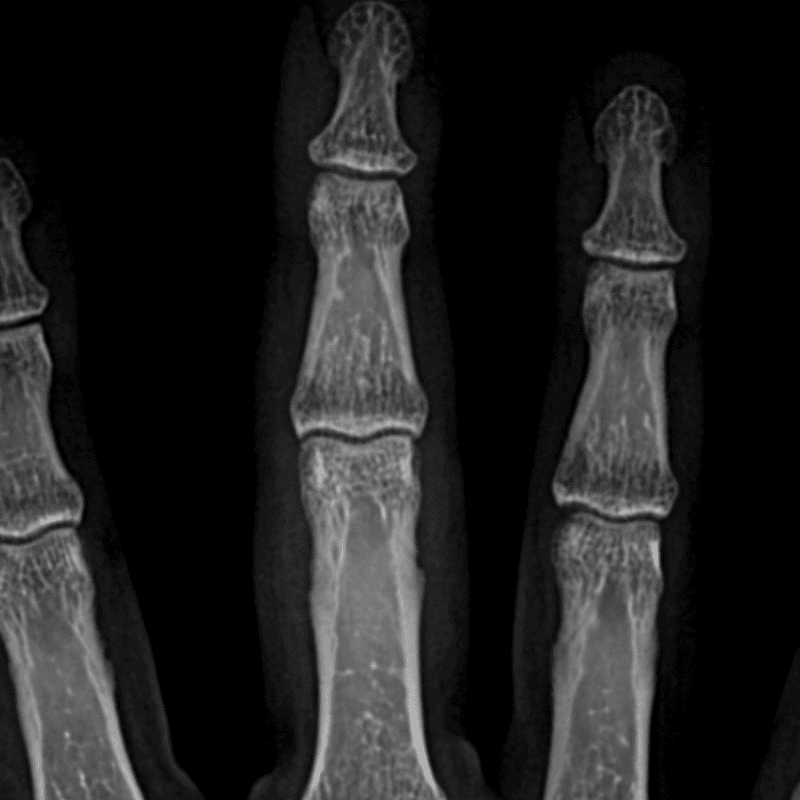

Simuliert den Dienst durch subtile oder schwierige Fälle und einige Normalbefunde.

30 Fälle